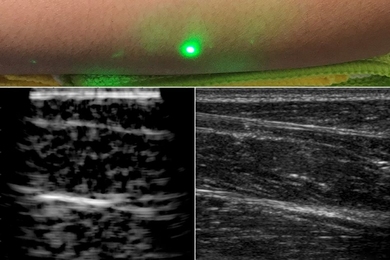

Technique may help remotely image and assess health of infants, burn victims, and accident survivors in hard-to-reach places.